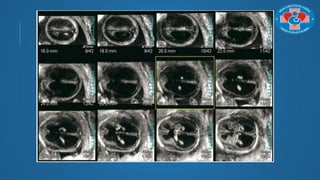

SỬ DỤNG TRONG 3 THÁNG ĐẦU THAI KÌ

Sử dụng trong 3 tháng đầu thai kì:

 Đếm số phôi trong trƣờng hợp chuyển/thụ thai quá nhiều

 Các bất thƣờng bề mặt

 Đo NT (Sono NT, Volume NT)

 Tính an toàn của trong 3 tháng đầu vẫn chƣa đƣợc xác định 

không dung thƣờng quy

SỬ DỤNG TRONG3 THÁNG ĐẦU THAI KÌ Sử dụng trong 3 tháng đầu thai kì:  Đếm số phôi trong trƣờng hợp chuyển/thụ thai quá nhiều  Các bất thƣờng bề mặt  Đo NT (Sono NT, Volume NT)  Tính an toàn của trong 3 tháng đầu vẫn chƣa đƣợc xác định  không dung thƣờng quy

SỬ DỤNG TRONG3 THÁNG ĐẦU THAI KÌ